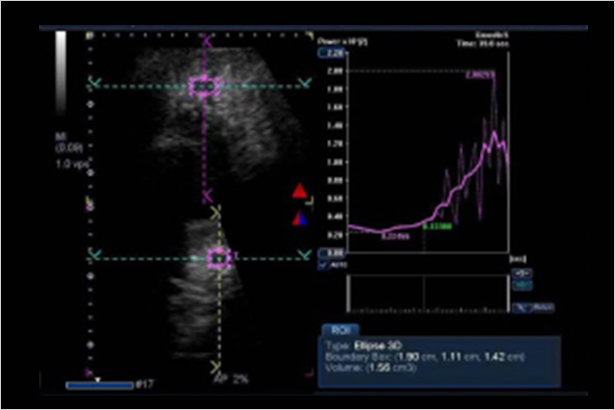

超聲造影定量和分析工具(如 CHi-Q 組件)幫助排除呼吸運動干擾,提高準確性、一致性以及檢查速度